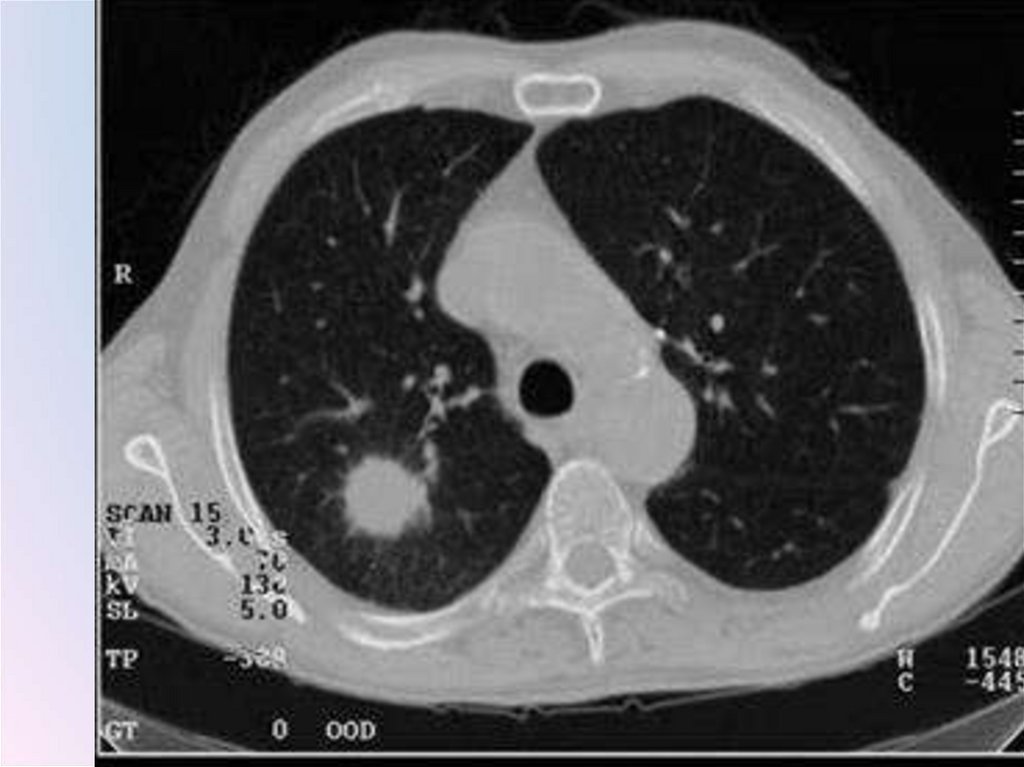

Патоморфологический субстрат шаровидного

образования: 1) туберкулезный инфильтрат;

2) туберкулома (инкапсулированный казеоз);

3) заполненная блокированная туберкулезная

каверна; 4) силикотические узлы; 5) «круглая»

неспецифическая пневмония; 6) недренированный абсцесс; 7) злокачественные опухоли;

лимфомы; 9) доброкачественные опухоли

(наиболее часто гамартомы, содержащие

хрящевую ткань); 10) сосудистые

образования; 11) кисты, заполненные

жидкостью; 12) инфаркт; 13) гематома; 14)

осумкованный экссудат в междолевой плевре

(последний не является истинно легочным, внутрипаренхиматозным образованием, однако, замкнутый листками плевры,

оказывается расположенным внутри легкого)